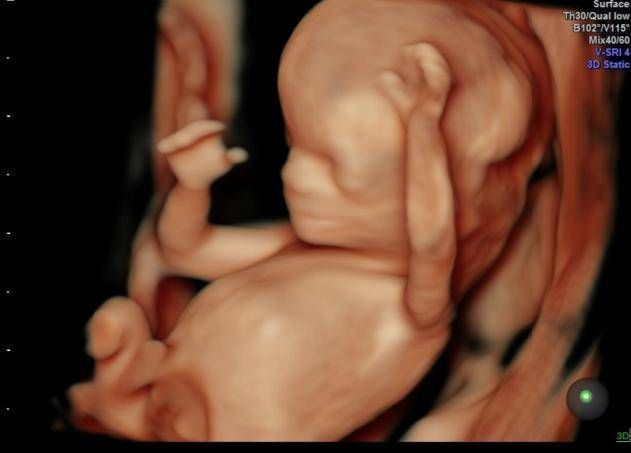

孕期产检,相信不少孕妈妈都很期待四维排畸这一项了,四维彩超排畸检查有不少准妈妈也想带着准爸爸进去,一同分享这其中的喜悦。

【为什么有些医院做四维彩超不让家属陪同这些原因,大家有权知道】小茹怀孕24周左右的时候,身边朋友提醒她这个时候需要做四维大排畸了,不仅能知道胎宝宝发育状况,还可以提前看到宝宝的长相。

3、保护胎儿的性别:四维检查会检查出胎儿的性别,而且胎儿性别是孕妈及家人最关心的一件事。如果家属入内,有的出于好奇,有的出于性别选择,都会询问医生胎儿的性别。而医生鉴定胎儿性别如果不是医学上需要的,这是违法的,所以医生不会去触碰这个红线,家属不论怎么询问,医生都会保护好胎儿性别。